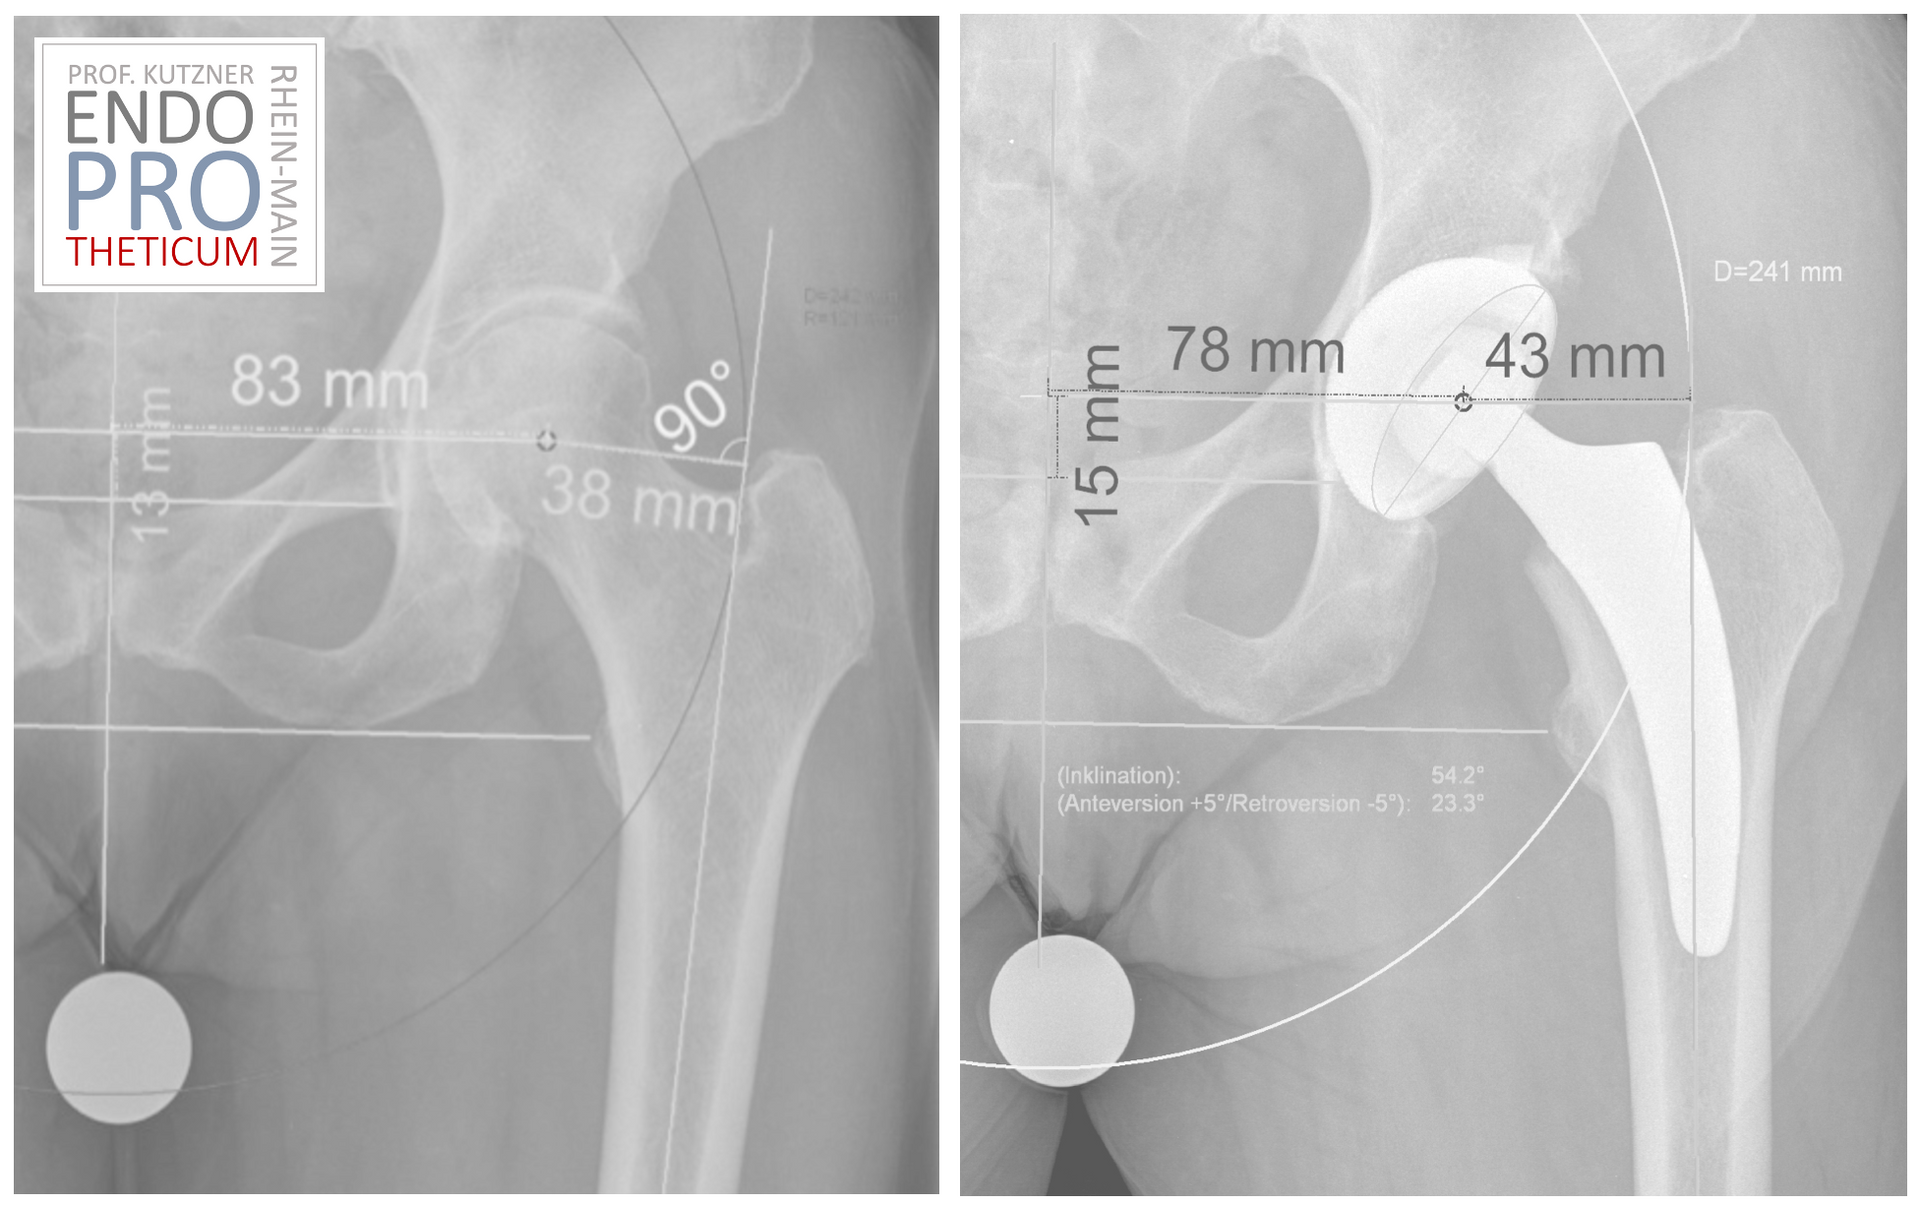

لقد تطورت جراحة مفاصل الورك في السنوات الأخيرة، ومن المجالات التي أصبحت ذات أهمية متزايدة هي الأطراف الاصطناعية قصيرة الساق. توفر هذه الغرسات المبتكرة بديلاً واعداً للغرسات التقليدية ويمكن أن تغير الطريقة التي نعالج بها مشاكل الورك. في هذه المقالة، نلقي نظرة فاحصة على مستقبل تقويم مفاصل الورك ولماذا تلعب الأطراف الاصطناعية قصيرة الجذع دورًا حاسمًا فيه.

وقد تم تطوير الأطراف الاصطناعية قصيرة الجذع لمعالجة بعض المشاكل

من الغرسات التقليدية. بفضل طول العمود القصير

أنها توفر استقرارًا وحركة أفضل لمفصل الورك. مرارا وتكرارا

في كثير من الحالات، يتم تمكين تقنية جراحية طفيفة التوغل، مما يؤدي إلى

يمكن أن يؤدي إلى فترات تعافي أقصر وتقليل الانزعاج بعد العملية الجراحية.